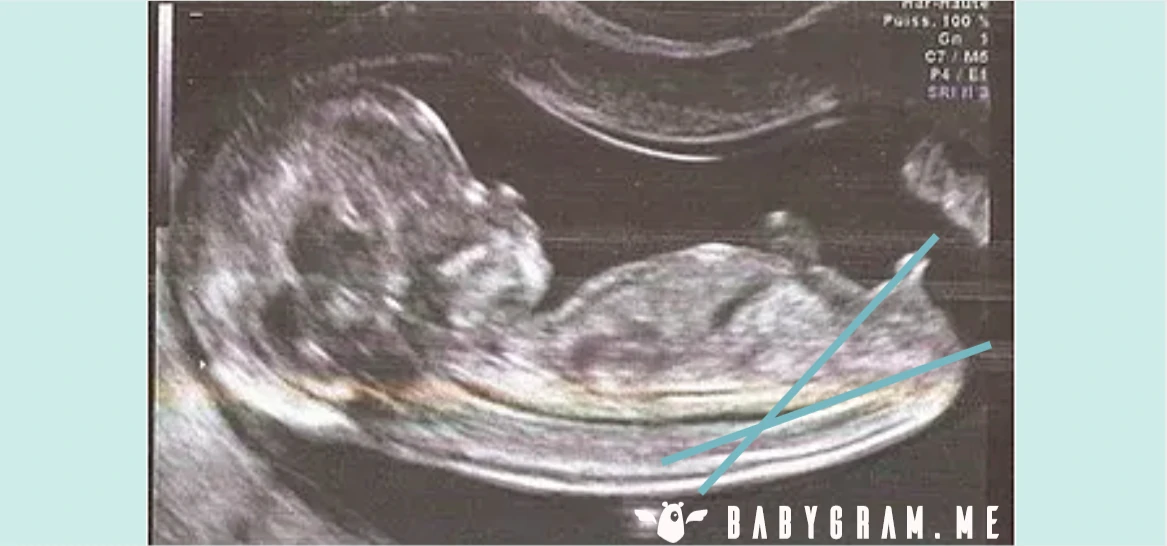

Our experts use the well-known nub theory to help identify the gender of your unborn child based on your first trimester ultrasound. The nub is your child's indeterminate sexual organ, which will transform into a penis or a clitoris during the second trimester of pregnancy. In practice, the nub theory consists of analyzing the angle between your child's nub and its spine during the ultrasound. You can see a girl and a boy example on the images below and read more explanations in our detailed article.

BABYGRAM uses the genital bud method to analyze your ultrasound when the conditions for this method to be accurate are met. This method has an average reliability greater than 90% for ultrasounds performed after 12 weeks of pregnancy (14 weeks after your period) and for fetuses whose cranio-caudal length is greater than 60mm, when the ultrasound image reveals the entire nub.